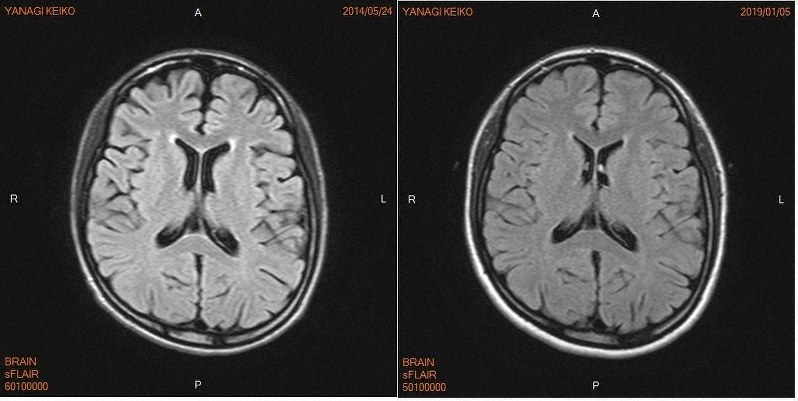

正常画像と並べてわかるシリーズ 正常画像と並べてわかる 頭部mri 改訂版 ここが読影のポイント 羊土社